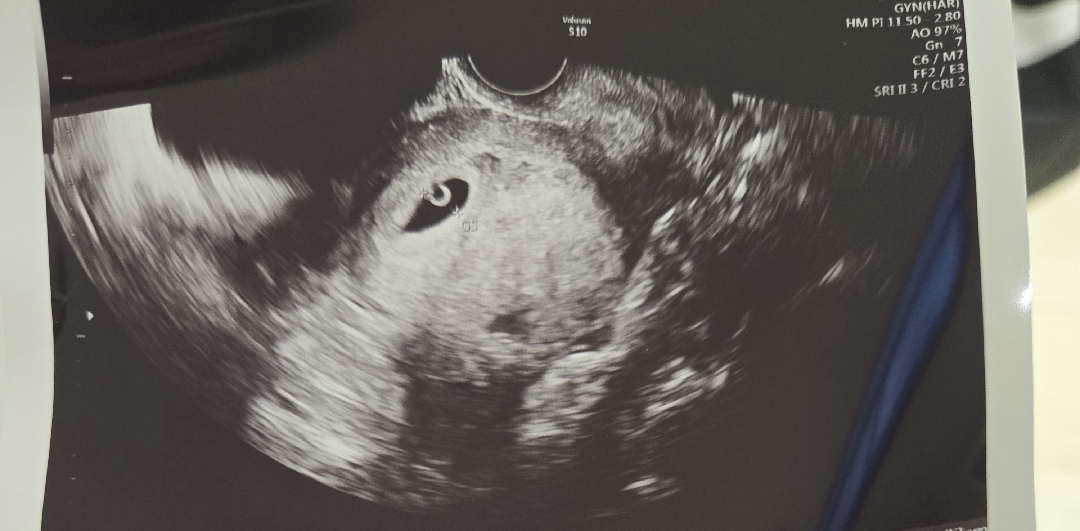

촘파사진봐주세요

집 잘지었겠져?

넹 난황도 잘보여요 ㅎㅎㄹ

예쁜집이네요! 각도마다 집크기가 다르더라구여!! 너무 걱정마세요!